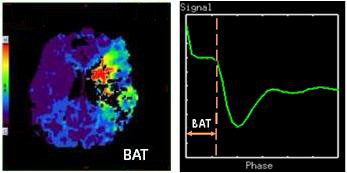

Bolus Arrival Time

Bolus Arrival Time (BAT): time from scan start to tracer bolus arrival of bolus at tissue.